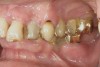

D2 root-surface lesions (Figure 3) are characterized by the dull surface demonstrated with D1 root-surface lesions. In addition, the surface feels sticky and somewhat soft when palpating with the side of the explorer. The examiner may notice that the root surface slightly resists gentle exploration over the root surface with the side of the explorer. Color changes in D2 root-surface lesions may range from dark yellow to orange/light brown. No cavitation of the root surface exists. The recommended treatment for D2 root-surface lesions includes remineralization with products (pastes and varnishes) containing fluoride, calcium, and phosphate. If the area is in the esthetic zone, the patient may request restoration, despite intact root structure.

It is common for practitioners to press the tip of the explorer into these root surfaces and decide to restore these “carious” areas. When pressing an explorer into a D2 root surface, a clinician may feel a definite softened surface or a “stick.” It is vital to either use the side of the explorer or visual inspection when determining these lesions. Aggressive exploration with the tip of the explorer may cavitate these root surfaces, which can lead to mechanical damage of the root surface and a decrease of the likelihood of successfully remineralizing the surface.

Figure 3  This root surface has a dull surface and is discolored. This indicates the progression of the demineralization/caries process. No cavitation has occurred due to this process. This root surface will feel slightly tacky and softened when exploring with the side of the explorer.

Figure 3